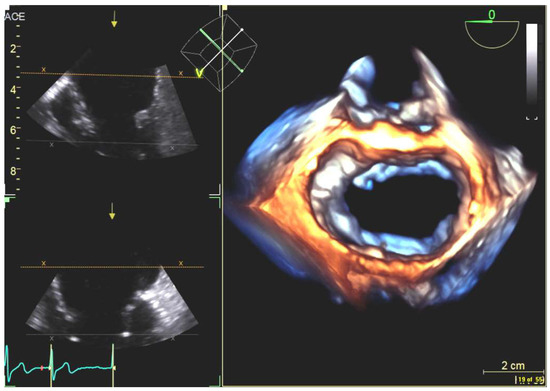

4.2.1. Transseptal Puncture

4.2.2. Left Atrial Appendage Occlusion

4.2.3. Mitral Valve Repair

4.2.4. Atrial Septal Defect Occlusion

4.2.5. Paravalvular Leak Closure

4.2.6. Transcatheter Aortic Valve Replacement